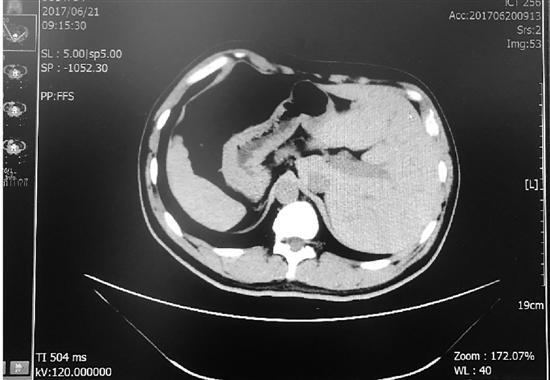

圖為影像片

得知需要手術,張先生脫口而出的第一句話就是:“我是個鏡面人。”這意味著,他的心、肝、脾等臟器都在與常人相反的位置,腸道也是如此。“一般人的大腸是順時針的,闌尾在右側,而鏡面人的大腸是逆時針方向,闌尾在左側。”

“鏡面人是完全性內臟反位的俗稱,通常表現(xiàn)為胸腔、腹腔器官及解剖結構的完全左右反位。”盧敏醫(yī)師介紹,“鏡面人”是在人體胚胎發(fā)育過程中,只有父母體內基因的一個位點同時突變才會出現(xiàn),這種突變是隱性遺傳,遺傳幾率很低,發(fā)生率約為百萬分之一。